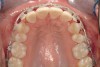

Figure 5j  A 50-year-old female concerned about appearance and bite. Jackscrew appliance was placed after 6 months of orthodontic alignment (A to C). Patient was missing No. 11 and had A-P and transverse maxillary deficiencies with anterior and left posterior crossbites. Bite was opened with glass ionomer cement. Single-tooth osteotomies were performed on Nos. 6 and 12 and multiple-tooth osteotomies were completed on Nos. 3 to 4, 7 to 10, and 13 to 14 (D). Corticotomies were also performed on Nos. 7 to 10 segment. Postsurgery 21 days (E). Jackscrews were activated 0.5 mm/day after 5-day latency period. Note pure translation of segments without tipping. Result 8 months postsurgery (F to I). Tooth No. 12 was converted to a canine, and an implant was placed in regenerate bone. Note amount of alveoloskeletal correction and increase in volume of maxillary arch. Also note in Figure 6C and Figure 6H the amount of protraction of maxillary anterior segments while anchorage was maintained in posterior segment. Restorative dentist: Michael E. Carter, DDS.

Figure 5j

Figure 6a  A 50-year-old female concerned about appearance and bite. Jackscrew appliance was placed after 6 months of orthodontic alignment.

Figure 6a

Figure 6d  Figure 6d Patient was missing tooth No. 11 and had A-P and transverse maxillary deficiencies with anterior and left posterior crossbites. Bite was opened with glass ionomer cement. Single-tooth osteotomies were performed on teeth Nos. 6 and 12 and multiple-tooth osteotomies were completed on teeth Nos. 3 to 4, 7 to 10, and 13 to 14.

Figure 6d

Figure 6e  A 50-year-old female concerned about appearance and bite. Jackscrew appliance was placed after 6 months of orthodontic alignment (E). Jackscrews were activated 0.5 mm/day after 5-day latency period. Note pure translation of segments without tipping.

Figure 6e

Figure 6f  Jackscrews were activated 0.5 mm/day after 5-day latency period. Note pure translation of segments without tipping. Result 8 months postsurgery. Tooth No. 12 was converted to a canine, and an implant was placed in regenerate bone. Note amount of alveoloskeletal correction and increase in volume of maxillary arch. Also note in Figure 6c and Figure 6c the amount of protraction of maxillary anterior segments while anchorage was maintained in posterior segment. Restorative dentist: Michael E. Carter, DDS.

Figure 6f